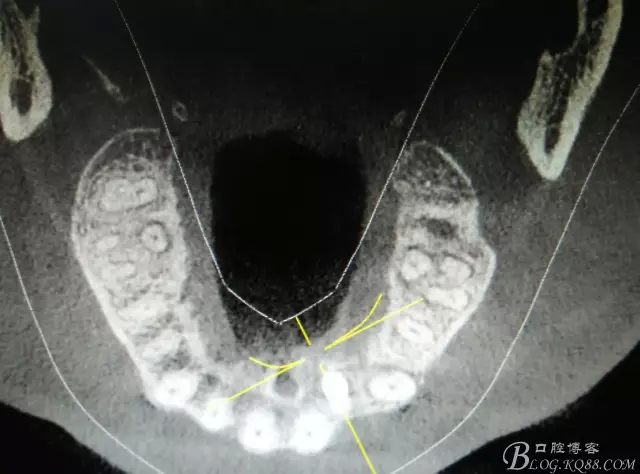

圖2.CBCT的三維成像及縱剖面、水平面影像

圖11.術(shù)后的CBCT檢查: